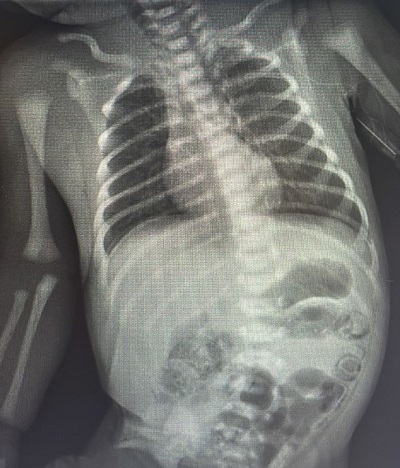

Recién nacida a término (RNT) de peso adecuado para la edad gestacional, sin antecedentes de interés, alimentada con lactancia materna exclusiva (alguna toma de fórmula puntual en Maternidad), que acude a la primera revisión del RN a los 8 días de vida. Se objetiva una pérdida ponderal del 10% respecto al nacimiento e ictericia. Se deriva al hospital, donde ingresa para fototerapia e inicio de lactancia mixta. En las horas siguientes empieza con intolerancia digestiva, vómitos y distensión abdominal. Se realiza analítica con neutrofilia leve y radiografía abdominal con distención de asas y signos de neumatosis intestinal. Ante dichos hallazgos, se deja a dieta absoluta y se inicia antibioterapia. A las 8 horas se repite analítica, donde presenta leucocitosis con más neutrofilia y elevación de reactantes de fase aguda con procalcitonina de 17,70 ng/ml. En la radiografía abdominal presenta aumento de la neumatosis intestinal. Ante la sospecha de enterocolitis necrotizante (NEC), se traslada a un hospital de tercer nivel. A las 36 horas de ingreso presenta empeoramiento clínico, evidenciándose en control radiológico neumoperitoneo por perforación intestinal (Fig. 1), precisando cirugía urgente con colostomía.

Figura 1. Neumoperitoneo por perforación intestinal

Figura 1. Neumoperitoneo por perforación intestinal.